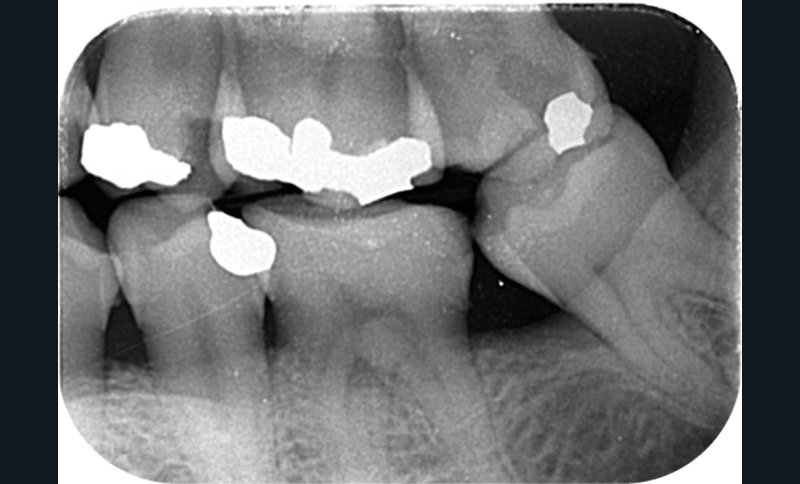

Cette version, quand elle se produit, modifie les espaces interdentaires et complique l’hygiène proximale des patients. Des caries peuvent alors se développer en interproximal sans que cela soit forcément visible à l’examen visuel (fig. 3 et 4). Les radios de type bite-wing (rétro-coronaires) prennent alors tout leur sens (fig. 5 et 6).